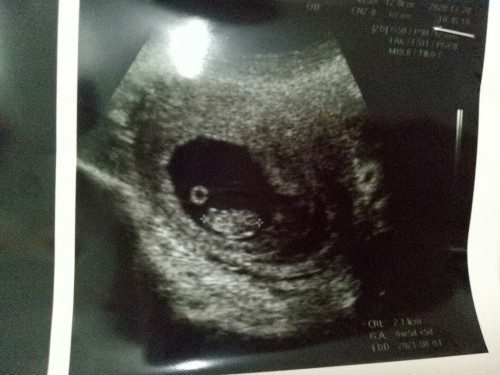

Salam.hi mom to be n mom outhere. Saya baru ini dh buat apoitment buka buku di kkia..sbb bulan 5 baru nih saya keguguran Hasil scan di kkia usia kehamilan 8 minggu 5 hari tapi dari info kata belakang jnin bby yg dh nmpk jantung tuh mcm ada lgi 1 kantung tp dr kata kantung kosong so dr mtk lagi 2 minggu datang tuk scan lgi bru blh taw. Mom out there ada yy prh jadi mcm nih?adakah kantung kosong tuk kemingkinan kembar tp blm nmpk sgt sbb masih kecil atau apa ya mom?Saya keliru dan juga risau sbb nih kali 2 preggy n suami memang ada kembar#mommybuntu #pregnancy #Nanya #bantusharing #firstbaby

Salam.hi mom to be n mom outhere. Saya baru ini dh buat apoitment buka buku di kkia..sbb bulan 5 baru nih saya keguguran Hasil scan di kkia usia kehamilan 8 minggu 5 hari tapi dari info kata belakang jnin bby yg dh nmpk jantung tuh mcm ada lgi 1 kantung tp dr kata kantung kosong so dr mtk lagi 2 minggu datang tuk scan lgi bru blh taw. Mom out there ada yy prh jadi mcm nih?adakah kantung kosong tuk kemingkinan kembar tp blm nmpk sgt sbb masih kecil atau apa ya mom?Saya keliru dan juga risau sbb nih kali 2 preggy n suami memang ada kembar.#bantusharing #firstbaby #mommybuntu #seriusnanya #pregnancy